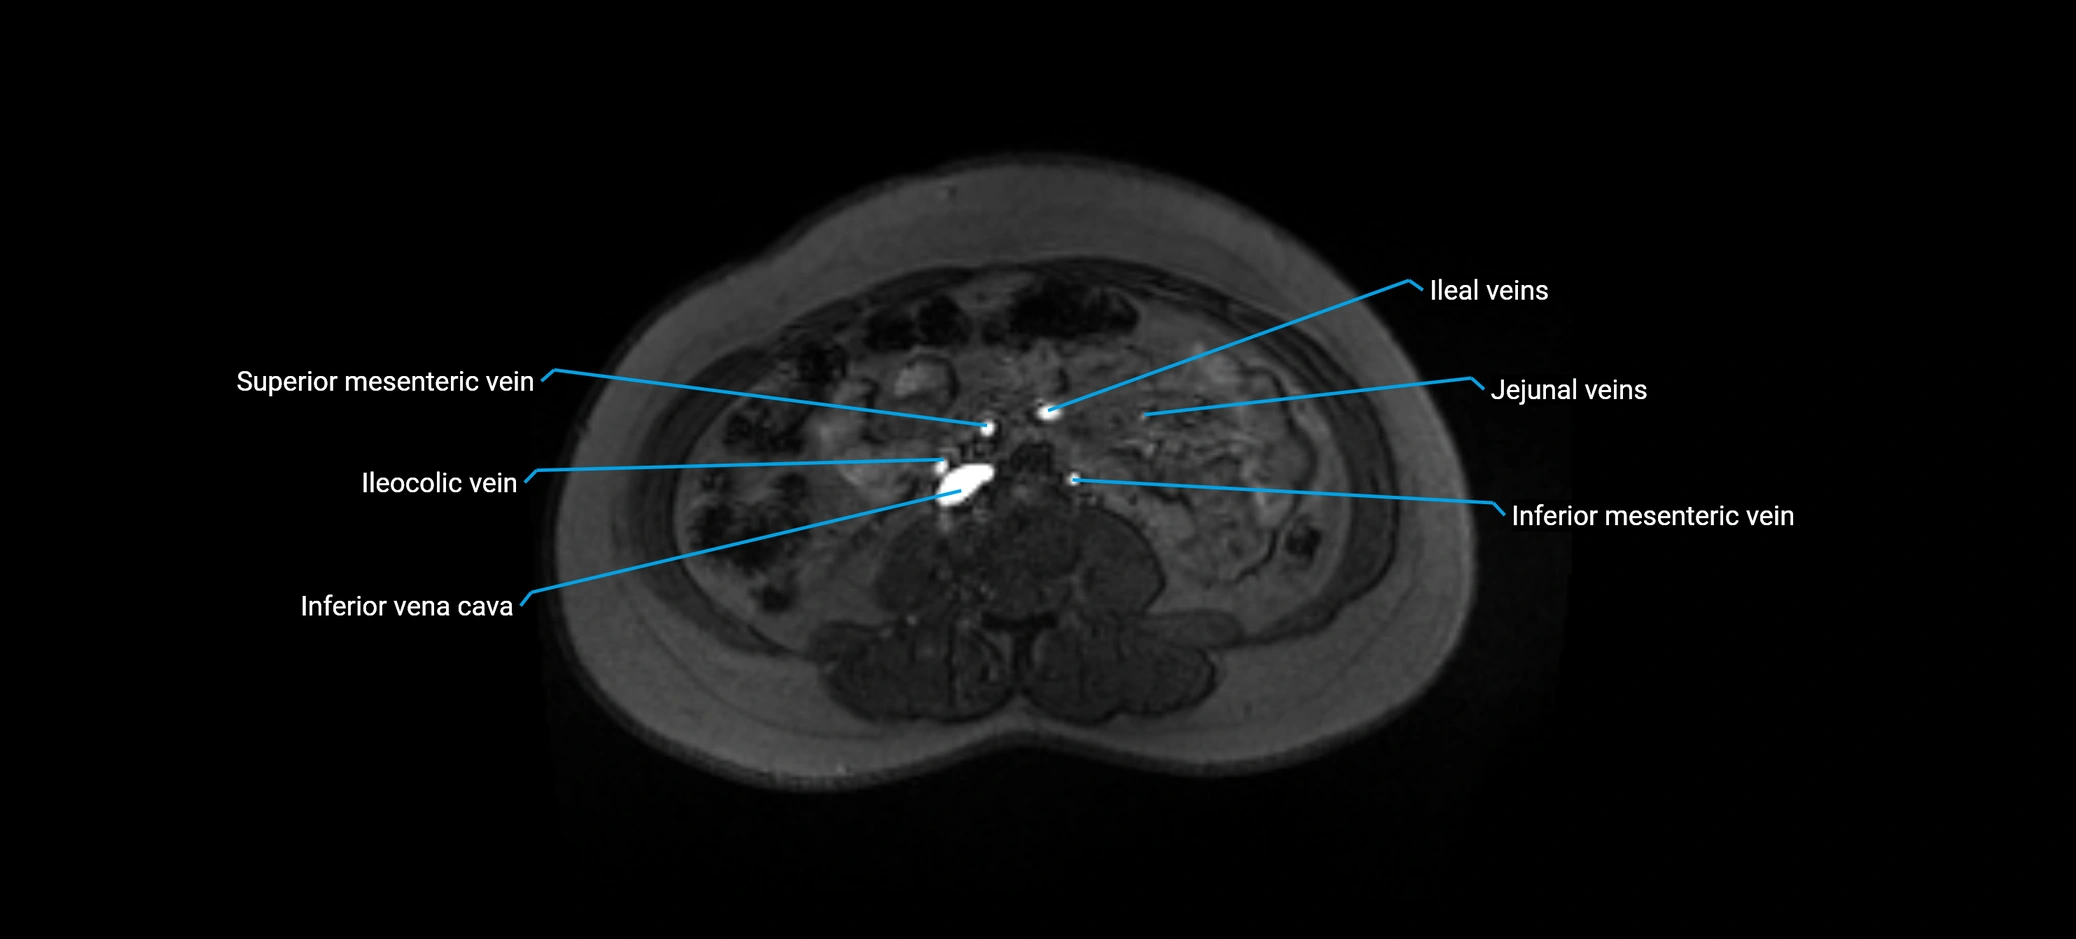

MRI image

image